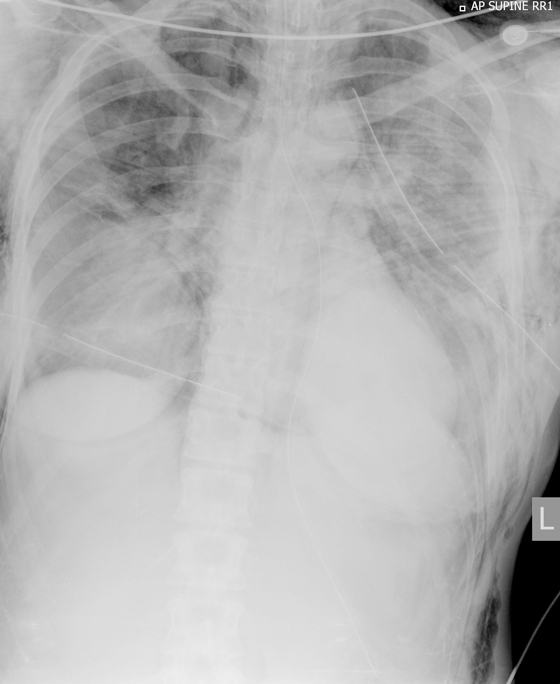

She was intubated and bilateral 32 Fr intercostal catheters were inserted, which improved ventilation and haemodynamic stability; the bilateral decompression needle catheters were removed. Chest x-rays (Box 1) showed extensive subcutaneous emphysema, multiple rib fractures and a persistent small right apical PTx.

1 Initial chest x-ray showing bilateral rib fractures, extensive subcutaneous emphysema and bilateral intercostal catheters